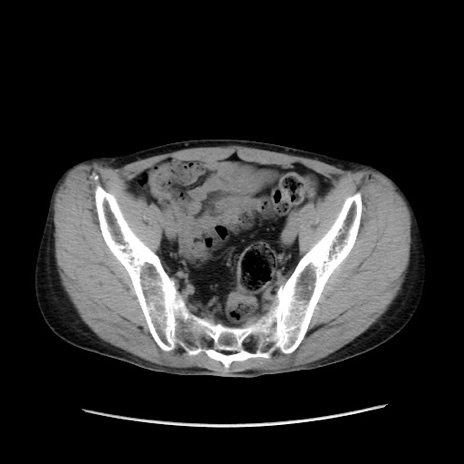

症例37(横断像)

【症例】40歳代 男性

【主訴】腹痛

【現病歴】4時間ほど前に電車に乗車中に臍部上より腹痛出現。徐々に増悪し起立困難となり、救急外来受診。生ものは数日食べていない。今朝お雑煮を食べた。

【身体所見】BT 36.8℃、BP 117/84mmHg、HR 91/min、SpO2 97%、苦悶様、腹部:臍上部広範囲圧痛あり、反跳痛±

【データ】WBC 8100、CRP 0.03